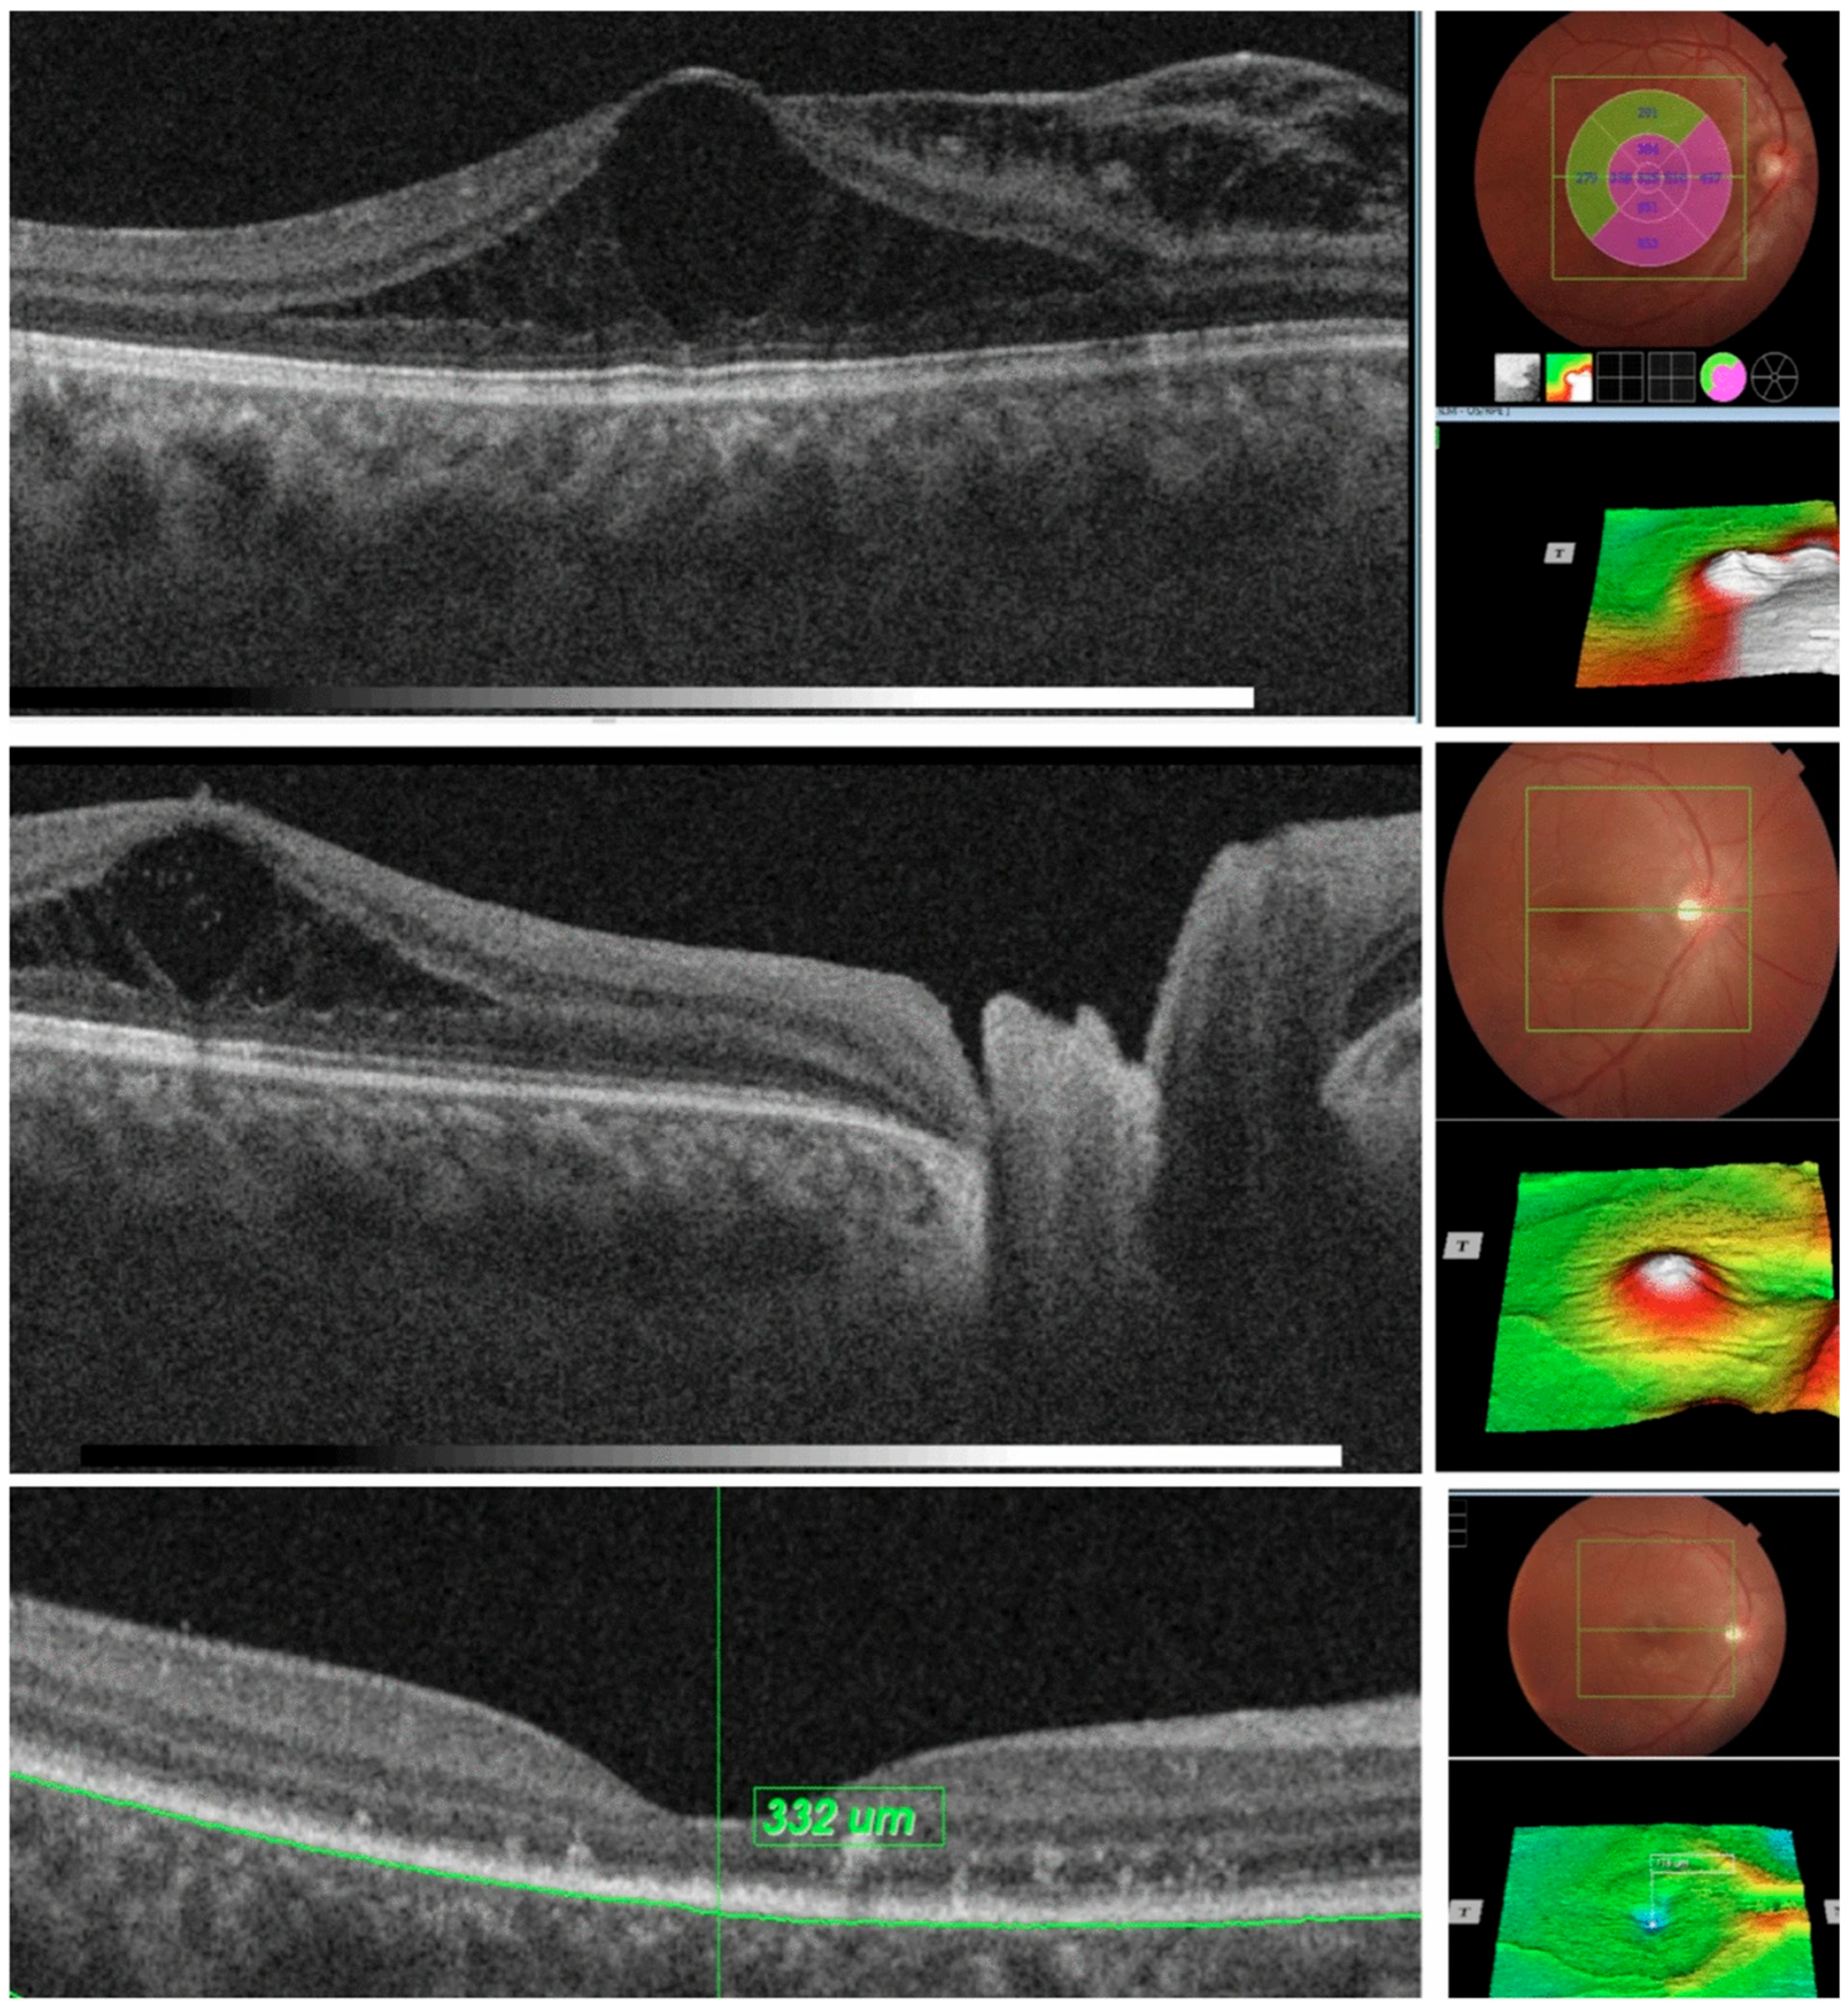

| 7. Optic Pit | Deep excavation of the optic disc with lamina cribrosa defect, herniation of nerve tissue, and associated serous macular detachment or intraretinal schisis. | Advanced OCT (EDI and SS-OCT) enables full visualization of pit morphology and fluid dynamics, improving diagnosis and monitoring of OP maculopathy. |

| 9. Morning Glory Anomaly | Large, funnel-shaped excavation of the optic disc with peripapillary gliosis, subretinal fluid, and abnormal communication with the subarachnoid space. | OCT reveals characteristic disc excavation and associated retinal detachment, aiding differentiation from other congenital optic nerve anomalies. |